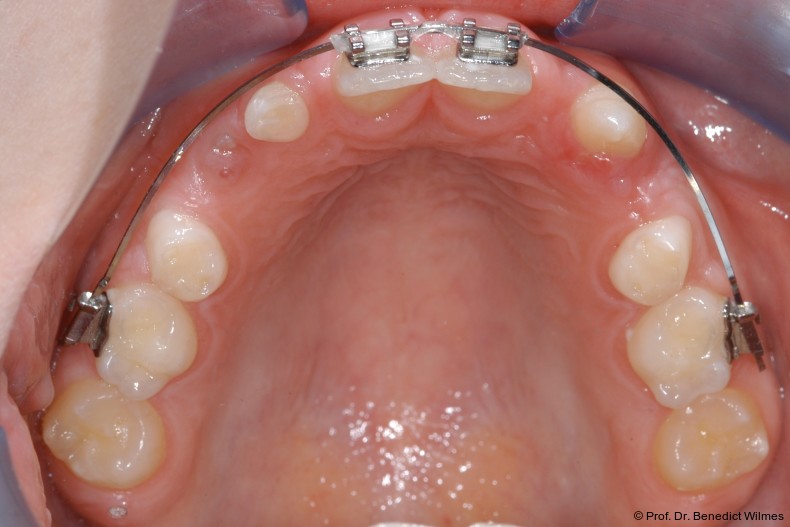

Ein 14-jähriger Patient wurde bei Aplasie der beiden oberen seitlichen Schneidezähne mit dem Ziel der beidseitigen Lückenöffnung kieferorthopädisch therapiert (Abb. 1a+b). Zum Ende der kieferorthopädischen Behandlung wurden zwei Miniimplantate in Regio 2er als temporärer Zahnersatz inseriert (Benefit System, PSM, 2 x 13 mm, Abb. 2a+b). Nach Abdrucknahme wurden Kronen auf den Peek-Abutments modelliert und diese mit Kunststoff auf die Abutments geklebt (Abb. 3a–d). In den Abbildungen 3 und 4 sind die klinischen und röntgenologischen Nachkontrollen innerhalb der nächsten achteinhalb Jahre dokumentiert. Man erkennt einen sowohl in der Höhe als auch in bukkopalatinalen Breite verbleibenden gesunden Knochen ohne Anzeichen einer Atrophie. Im Alter von 23 Jahren wurden die definitiven Implantate ohne die Notwendigkeit einer Augmentation eingesetzt (Abb. 5) und nach Einheilung prothetisch versorgt (Abb. 6a–e und Abb. 7a–c).

Nach Abschluss der kieferorthopädischen Pfeilerverteilung wurden zwei Miniimplantate in Regio 3er inseriert (2 x 13 mm). Nach Herstellung im Labor wurden Kronen auf den Miniimplantaten aufgeschraubt (Abb. 13+16a–d). Auch hier wurde darauf geachtet, dass die Kronen aus der Okklusion geschliffen wurden (Abb. 14). Bei den Nachkontrollen zeigten sich ebenfalls stabile Miniimplantate und ein entzündungsfreies Implantatlager ohne erkennbare Atrophie des Knochens (Abb. 15 und 16a–d).